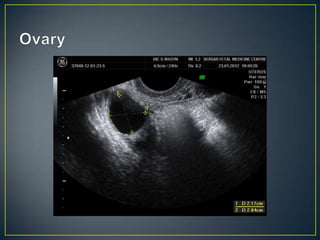

• When evaluating the adnexa, attempt should be first

made to identify the ovaries

• Once identifies, they should be used as reference point

• Ovaries should be examined in 2 orthogonal planes

• Ovaries may not be identified in cases before and after

puberty

• The normal fallopian tubes are not identified

• If any pathology is seen, size and sonographic nature of

the lesion should be documented

• Spectral , color and power doppler examination should

be performed

• Finally cul-de-sac should be examined posterior to the

uterus